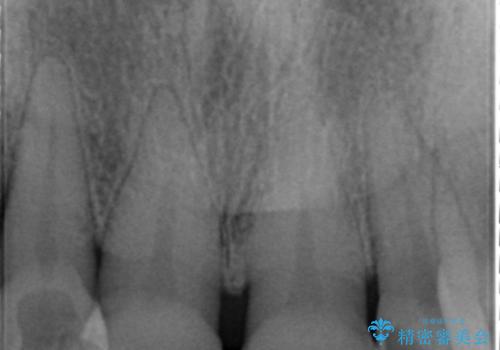

奥歯の咬み合わせがないことにより前歯に負担がかかり動揺が出ていました。

精査したところ右下の奥歯も歯周病により保存不可能な状態でした。

上の前歯は動揺を抑え、入れ歯の着脱にも耐えうるように被せ物を連結させることにしました。